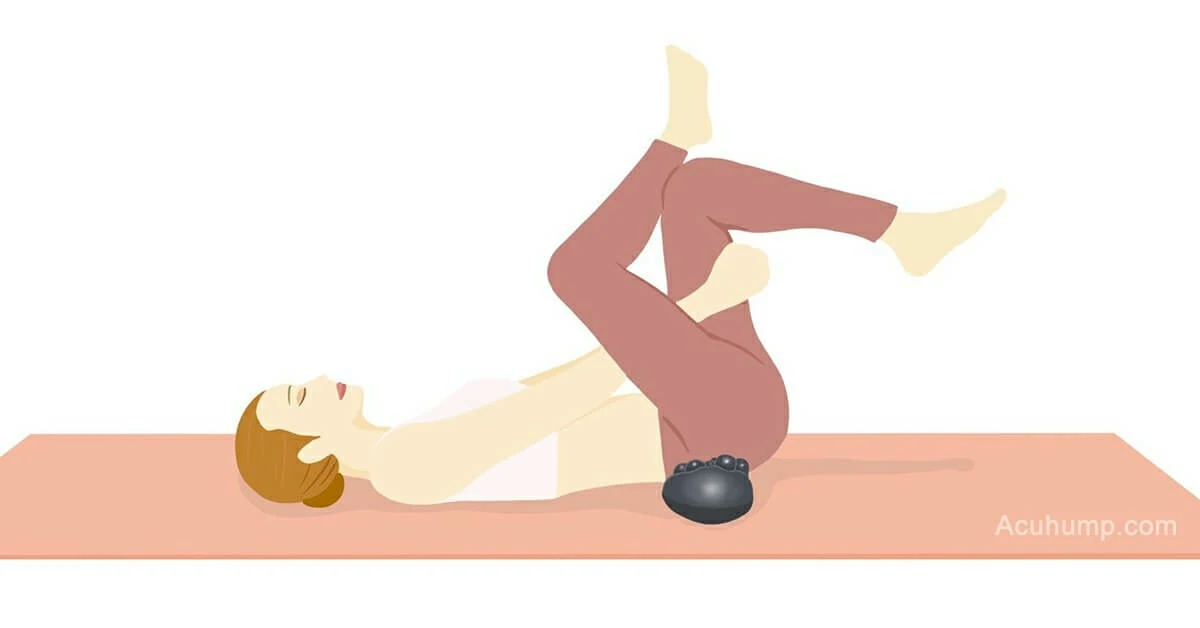

Using Acu-hump to massage the piriformis muscle is simple and effective. Simply place the tool under the affected area and use it to apply pressure to the muscle. You can adjust the pressure to your liking and focus on areas that feel particularly tight or painful. The raised bumps on the tool will work to target and release pressure in the muscle, promoting relaxation and pain relief.

In addition to massage, stretching with Acu-hump can also be incredibly effective for releasing tension in the piriformis muscle. By using the tool to support and extend the muscle, you can work to increase flexibility and reduce the likelihood of injury. Regular stretching exercises can help to prevent the development of piriformis syndrome, while also promoting overall health and well-being.

Incorporating Acu-hump into your daily routine is a simple and effective way to promote relaxation and ease tension in the lower body. Whether you are dealing with piriformis syndrome or simply looking for a way to release tension and improve flexibility, Acu-hump can be a valuable tool to have in your self-care arsenal.